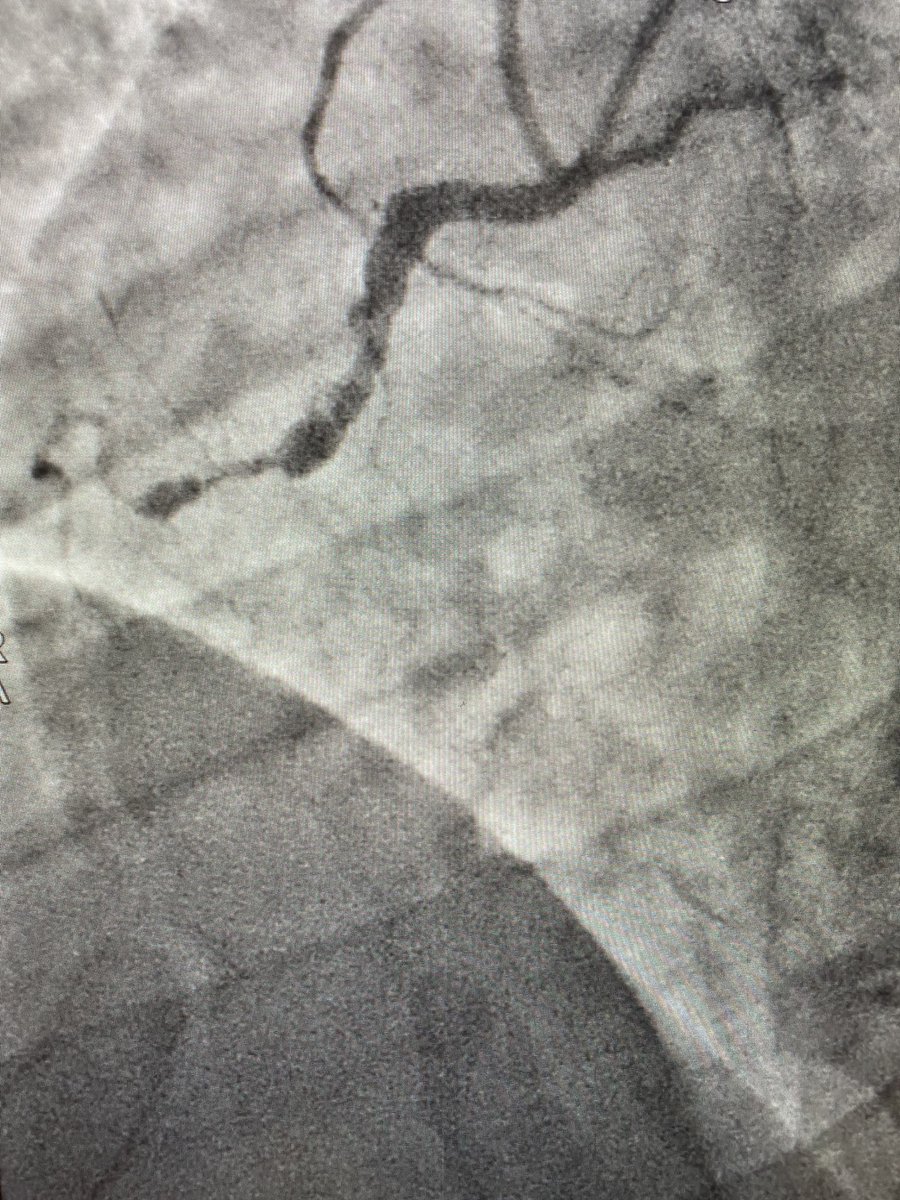

#ICFIT Subtotal occlusion of anomalous RCA (take off anterior/downward from left sinus, just beside LM stem). Diagnostic made in OSH (also crossover from radial to femoral) but report said they couldn’t PCI 🤷🏻‍♂️. Went femoral w/ multiples guides. Could probe and understand anatomy

evandrofilhobr's tweet image. #ICFIT Subtotal occlusion of anomalous RCA (take off anterior/downward from left sinus, just beside LM stem). Diagnostic made in OSH (also crossover from radial to femoral) but report said they couldn’t PCI 🤷🏻‍♂️. Went femoral w/ multiples guides. Could probe and understand anatomy